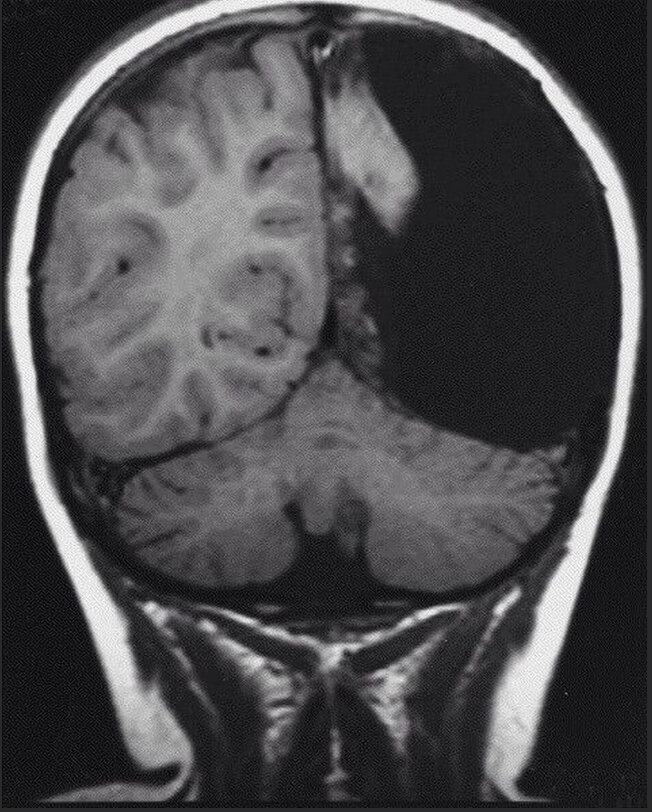

Пару лет назад, в подмосковную больницу попал 60-летний пациент с ишемической атакой (это как инфаркт, только чуток слабее). Человек чувствует себя неважно, теряется подвижность конечностей, но необратимых последствий нет. Причиной тому обычно становится нарушение кровообращения головного мозга, потому мужчине в первую же очередь сделали КТ(первый необходимый анализ в этой ситуации). Результаты томографии оказались весьма необычными. Ишемическая атака должна была произойти у мужчины в левой половине мозга, но какого же было удивление врачей, когда они узнали, что она напрочь отсутствует. Это был не результат какой-либо травмы, этот мужчина с рождения жил без половины мозга, что никак не помешало ему получить высшее образование, обжиться семьей и жить без проблем до 60-ти лет. Да и когда двигательные функции после этого самого попадания в клинику восстановились, то он спокойно ушел домой.

Имени пациент не стал раскрывать, дабы популярностью не усложнять себе жизнь. Ирония судьбы в том, что подобный ему ребенок уже не родиться, т.к. на ранних этапах отсутствие полушария увидят врачи и предложат матери прервать беременность, но в 50-х таких технологий не было, а потому герой обстоятельств увидел свет и спокойно дожил до своего возраста.

Отсутствие таких больших кусков мозга не как не отражается на интеллекте, но может повлиять на двигательные функции организма. Самое распространенное следствие этого «церебральный паралич».

Мозг удивительная штука, он имеет такую приколюху как «нейропластичность, что значит, что даже при отсутствии какой-то его части, оставшееся часть перестраивается под недостающую.